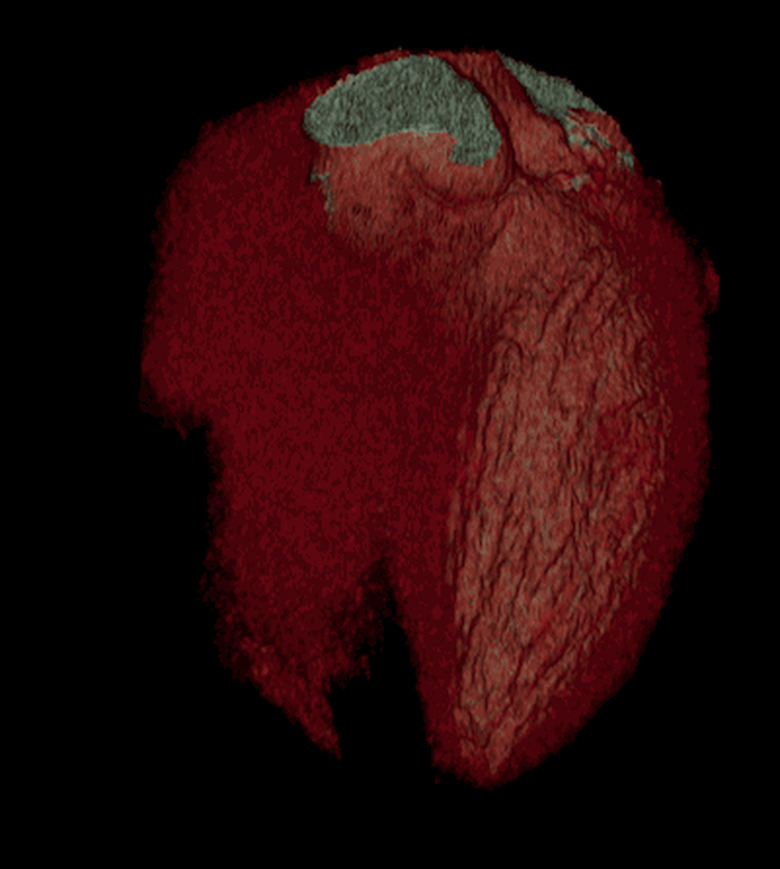

Few people enjoy having a CT scan. In a bleak hospital room, you have to lie flat on your back as a huge circular scanner shoots focused X-rays through your flesh and bones. The entire process can feel a little intimidating, which is why GE Healthcare has come up with the Revolution CT: a whisper-quiet and super-fast scanner that could make medical appointments a little quicker and less stressful for patients. The new machine, which is being trialled by the West Kendall Baptist Hospital in Florida, can capture an entire heart in a single beat, where each rotation takes just 0.28 seconds. That speed, combined with better contrast detection and noise reduction, could also reduce the doses of radiation required in each scan, potentially easing people's fears. In addition, none of these advancements should compromise the quality of the final 3D images — to prove its point, GE Healthcare has released some kinda gross, but undeniably beautiful GIFs of people's innards.

[Image Credit: GE Healthcare]